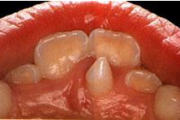

Ravijärgne seis. Jäävhammas on täielikult lõikunud.

) Röntgenülesvõte. Ülemise esimese jäävmolaari lõikumine on takistatud 2. piimamolaari tõttu

Esimese jäävmolaari ektoopiline lõikumine